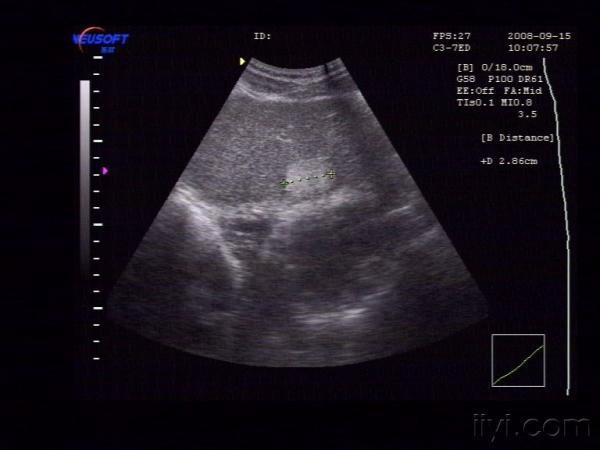

【贴图】肝脏血管瘤

体检发现左肝内一较强回声团,大小约为29X22X15mm,边界清,中央回声稍低。CDFI:未见异常血流信号